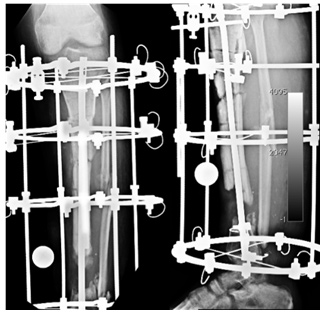

Our plastic surgeons were happy to do a double barreled fibula, and we fixed it with a long titanium plate that almost covered the bones completely.

| Double Barrelled Fibula and LCP fixation |